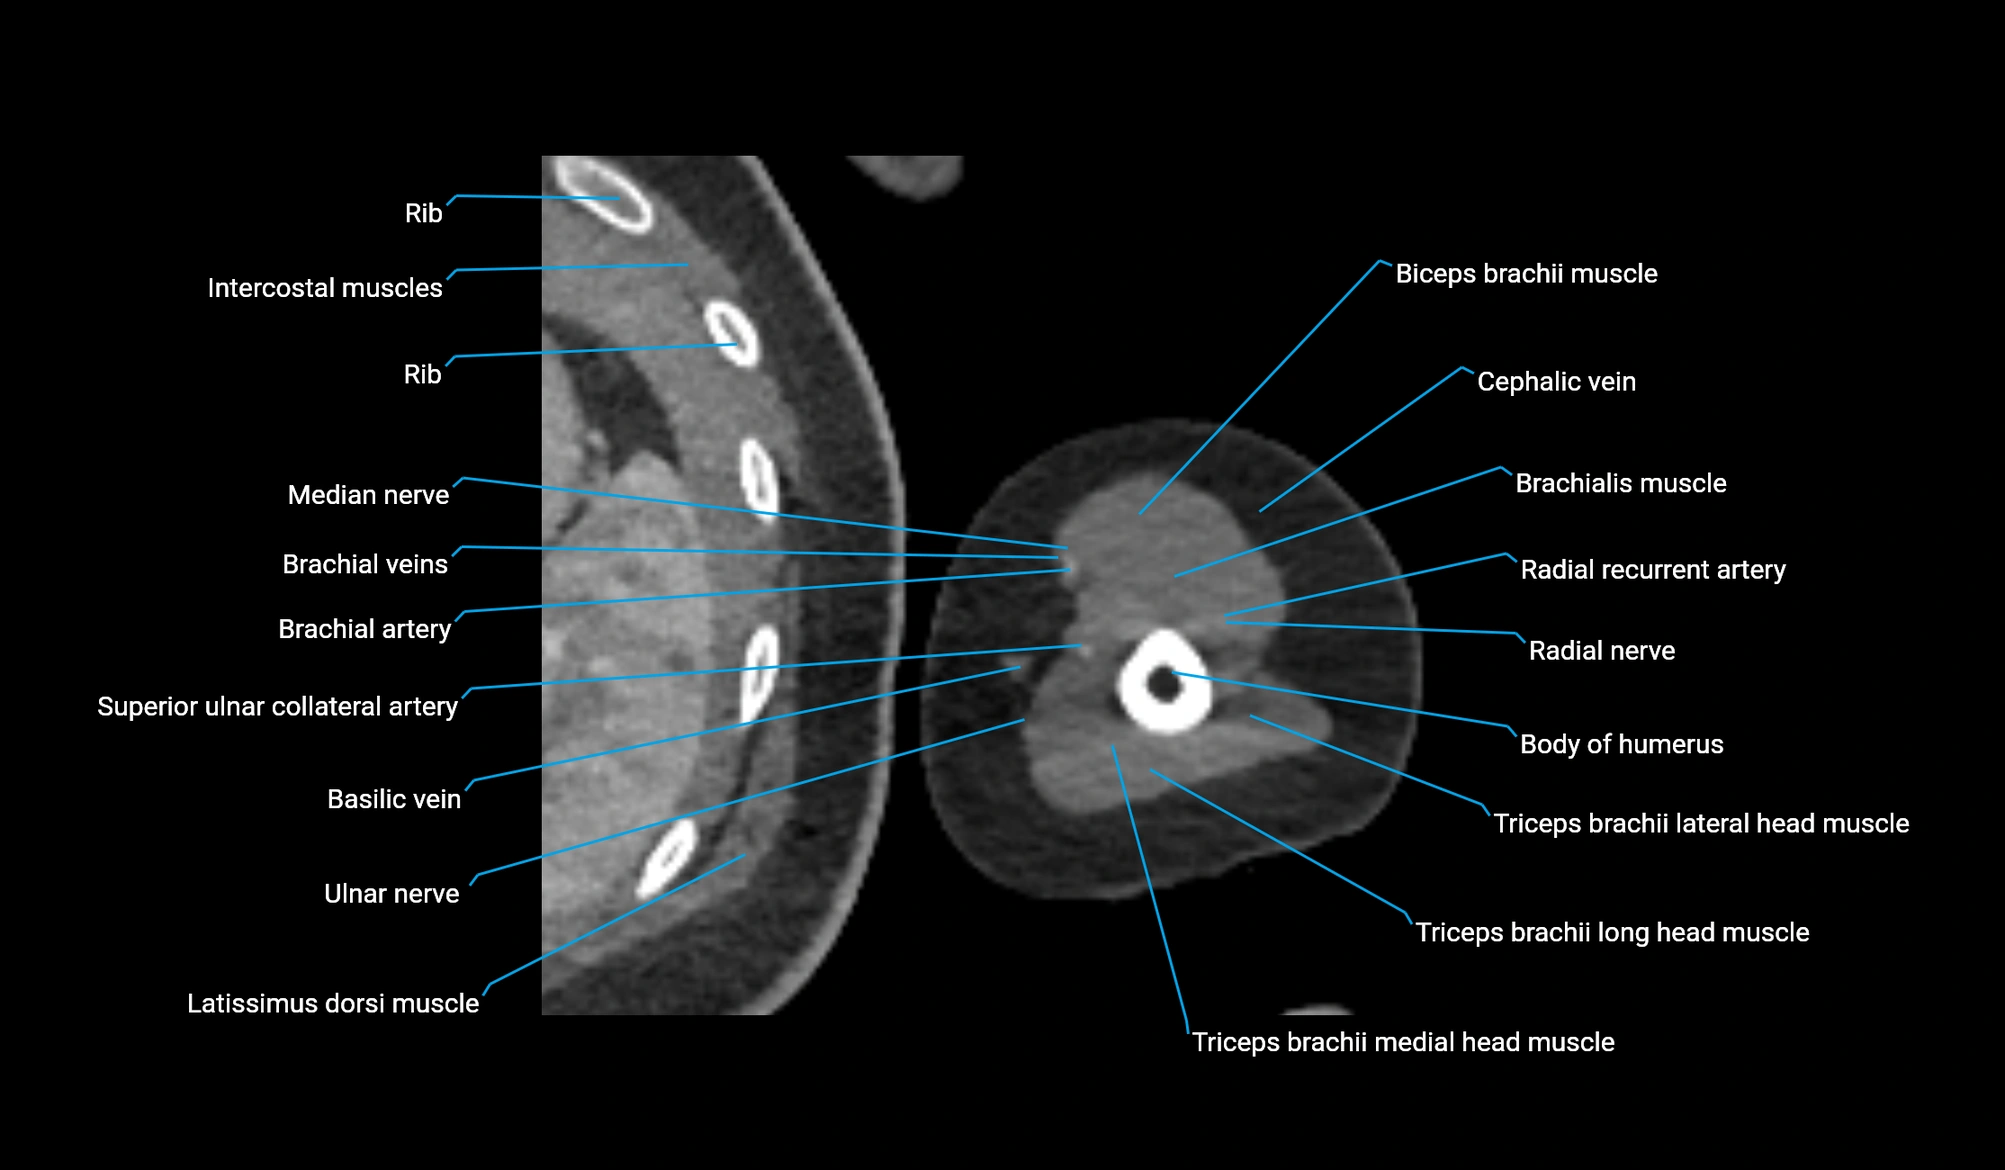

CT image